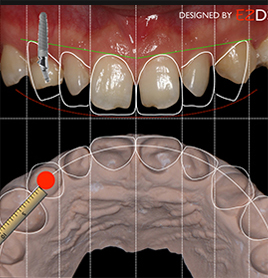

2口内制模 光学取模

模拟蜡型及牙体预备导板,完成标准化微创牙体预备。高精度取像技术直接获取牙齿数据